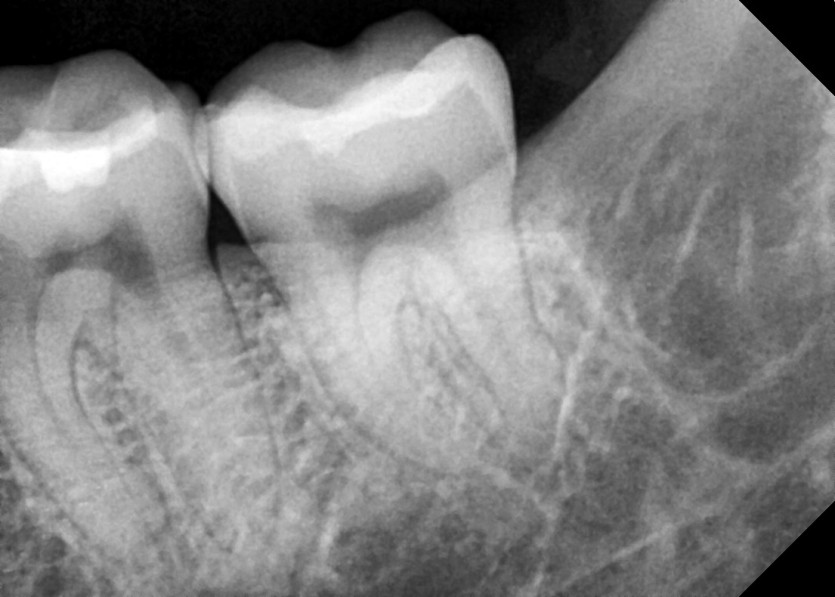

#38,48 사랑니 발치

구강 외과 전문의가 당일 발치했습니다.